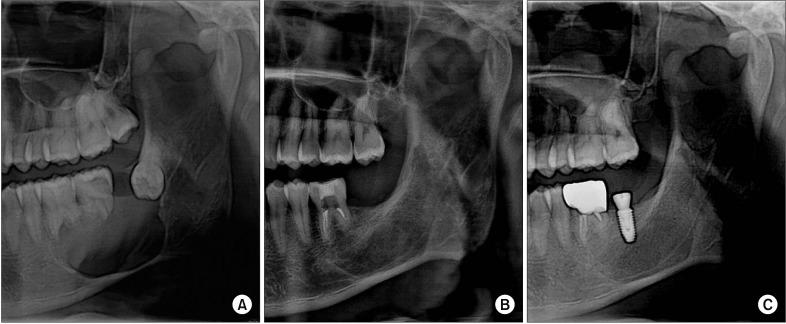

Ameloblastoma treatment varies based on the clinical, histopathologic, and radiographic characteristics. Aggressive surgical treatments, such as marginal or segmental resection, have traditionally been implemented, but some conservative surgical methods are also being introduced, including decompression, enucleation, or curettage. The aim of the present study was to evaluate the possibility of applying these conservative surgical treatments to ameloblastoma and to analyze the prognosis of the procedures and their healing aspects. Among all patients who visited our clinic (Department of Oral and Maxillofacial Surgery, Kyung Hee University Dental Hospital at Gangdong) from 2009 to 2017, three who had undergone conservative surgery were recruited. One of these three patients underwent both excision of the lesion and an iliac bone graft during the same procedure. In the other two patients, due to the size of the lesion, decompression was performed to reduce the size of the lesion, and then conservative surgical treatments followed. As shown in the cases of this study, patients were only treated with conservative surgical methods, such as decompression or enucleation. During the follow-up period, there were no recurrences. In conclusion, the use of conservative surgical treatment in ameloblastoma can be a reliable, safe, and successful method.